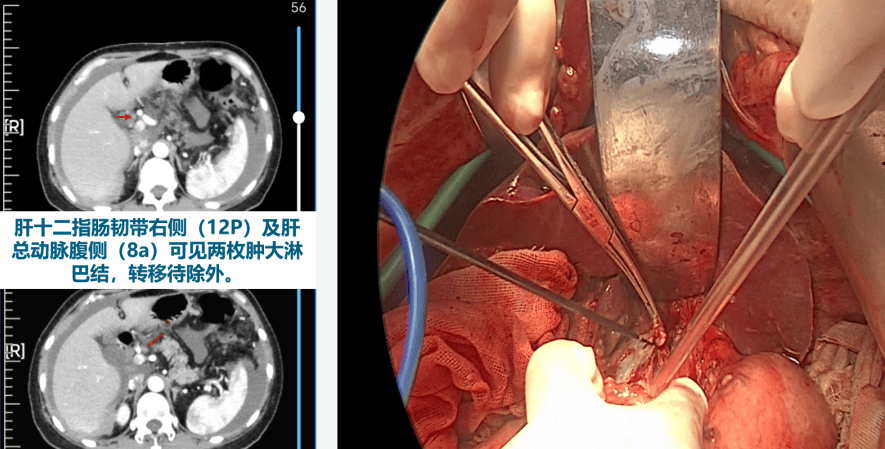

近年来,辽宁省肿瘤医院妇科团队在王丹波教授的带领下,已熟练掌握卵巢癌超根治术,规范了卵巢癌MDT全程管理模式,使患者五年生存率达到国内先进水平。卵巢癌手术治疗已从十多年前的盆腔器官切除联合腹膜后淋巴结清扫,发展至上腹腔器官切除及心膈角淋巴结切除。为实现真正的肉眼无残留(即卵巢癌R0标准),需充分探查并切除卵巢癌高转移区域,如膈肌、肝肾隐窝、膈肌脚、肝门淋巴结、肝胃韧带及肝叶间裂等。心膈角淋巴结亦是卵巢癌常见转移部位,研究显示近20%的病例存在该区域淋巴结转移。

本次中华医学会妇科肿瘤学中青年医师学术会议上,妇科放疗二·妇科六病区展示的研究成果提出了卵巢癌肝周转移的概念,公布了该区域转移的具体数据并分享了相关手术技巧,同时比较了不同手术入路处理卵巢癌心膈角转移的效果,为心膈角淋巴结切除术提供了可靠的循证医学依据。两项研究成果均入选大会论文发言,并受到妇科肿瘤学界同行的广泛关注。

肝门淋巴结切除

郭环同学作了题为《在多学科诊疗模式下卵巢癌肝及肝周转移手术的实践分析》的大会发言。她以详实的数据和清晰的逻辑,系统阐述了MDT模式在复杂卵巢癌围术期的精准应用,并结合具体资料对手术策略的选择与优化进行了深入分析。其汇报内容紧密贴合临床,兼具创新性与实用性,引发了在场妇科肿瘤专家的广泛共鸣与热烈讨论,获得一致高度评价。